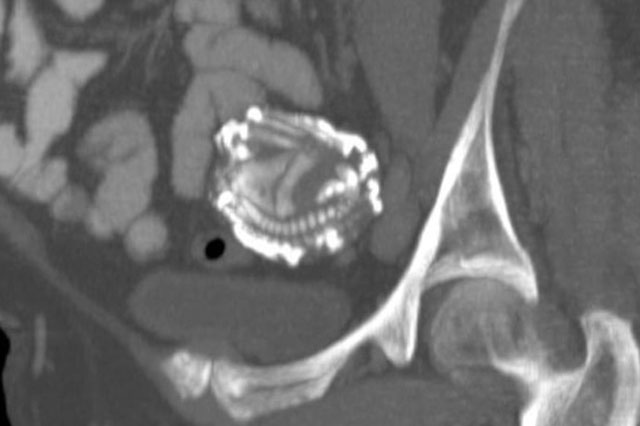

Một chuyên gia sản khoa đã vô cùng bất ngờ khi phát hiện một bào thai hoá đái trong bụng người mẹ hơn 15 năm.